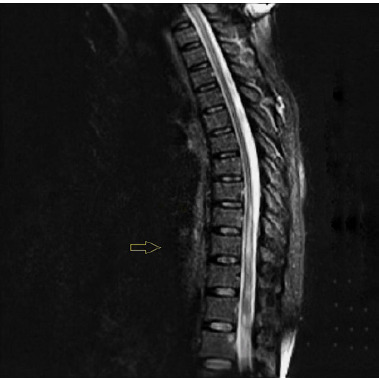

Case description: A 51-year-old woman presented with persistent holocranial headache, nausea, vertigo, and neurological deficits one month after a COVID-19 hospitalization. Neurological examination revealed hemiparesis, dysphagia, and ataxia. Imaging showed lesions in the central nervous system. A diagnosis of neurosarcoidosis was considered, supported by clinical criteria, imaging findings, and elevated ACE levels. Steroid therapy led to symptom improvement.